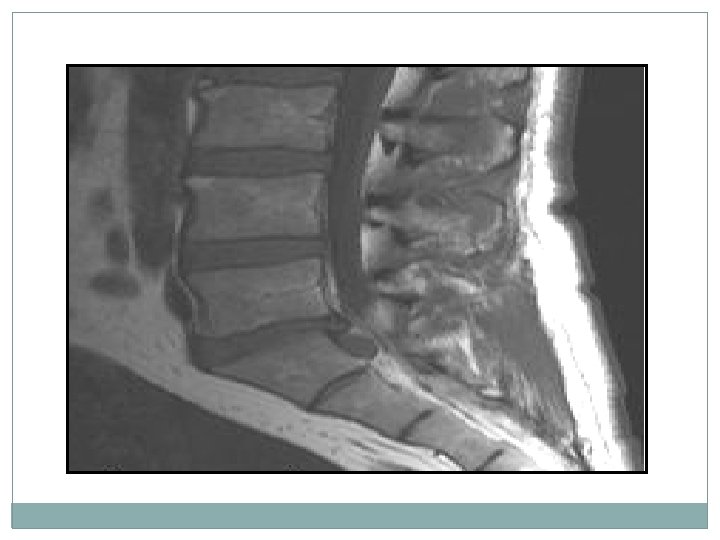

L’imagerie par résonance magnétique (IRM) lombosacrée �L'analyse des migrations herniaires et des sténoses canalaires associées. • L'exploration d'emblée de 1'ensemble des disques lombaires grâce aux coupes sagittales. • L'exploration du compartiment intradural.